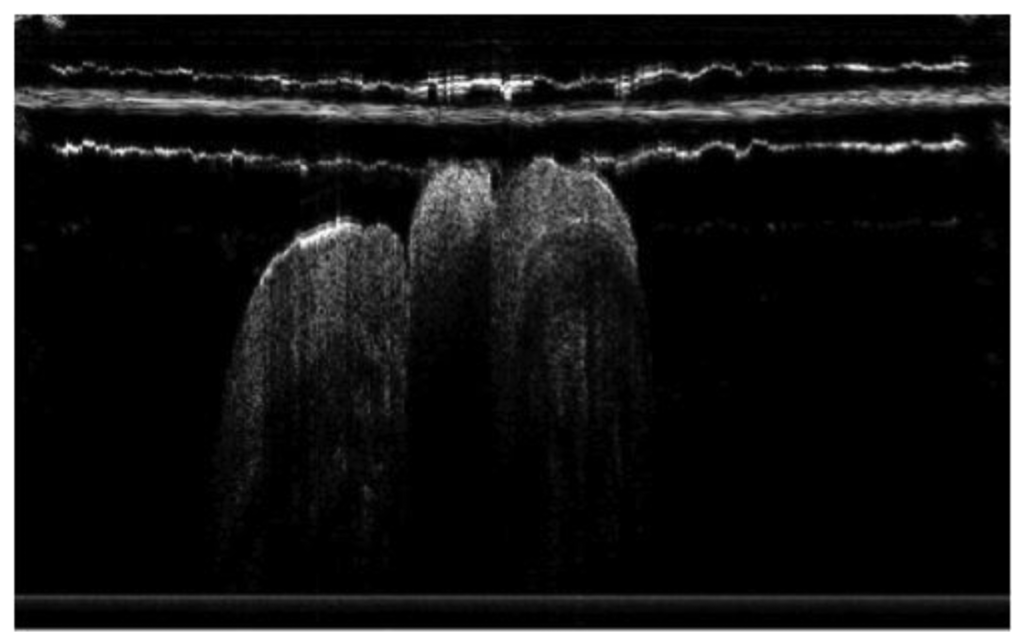

Periodontitis is one of the major chronic infectious diseases in the oral cavity. The prevalence of periodontitis is more than 50% among the population [77,78]. The WHO revealed that tooth loss resulting from severe periodontitis was found in 5%–15% of most worldwide populations in 2003 [79]. Additionally, recent studies have indicated that certain correlations between periodontitis and various systemic diseases exist [80–82]. Colston et al. were the first group to apply OCT in the diagnosis of periodontal disease [83,84]. They took in vitro images of dental and periodontal tissues from a young porcine model and compared these images to histological sections. Feldchteine et al. demonstrated epithelium and lamina propria of gingival mucosa [45]. However, the epithelium and lamina propria were not well differentiated because of the physical limitation. Baek et al. represented OCT images of periodontal ligaments during orthodontic movement of rat (Figure 11) [85]. Hsieh et al. demonstrated subgingival calculus in vitro. Tooth with subgingival calculus covered with 0.8 mm porcine gingiva was measured (Figure 12). Subgingival calculus is one of the pathogenetic factors of periodontal disease, so it is important to remove the residual subgingival calculus [28]. The refractive indices of enamel, dentin, cementum, and calculus were also measured as 1.625 ± 0.024, 1.534 ± 0.029, 1.570 ± 0.021, and 2.097 ± 0.094, respectively. The refractive indices help clinicians to distinguish calculus from normal tissues rapidly and correctly. With the aid of OCT, early detection of periodontal disease and monitoring of periodontal treatment could be very helpful.